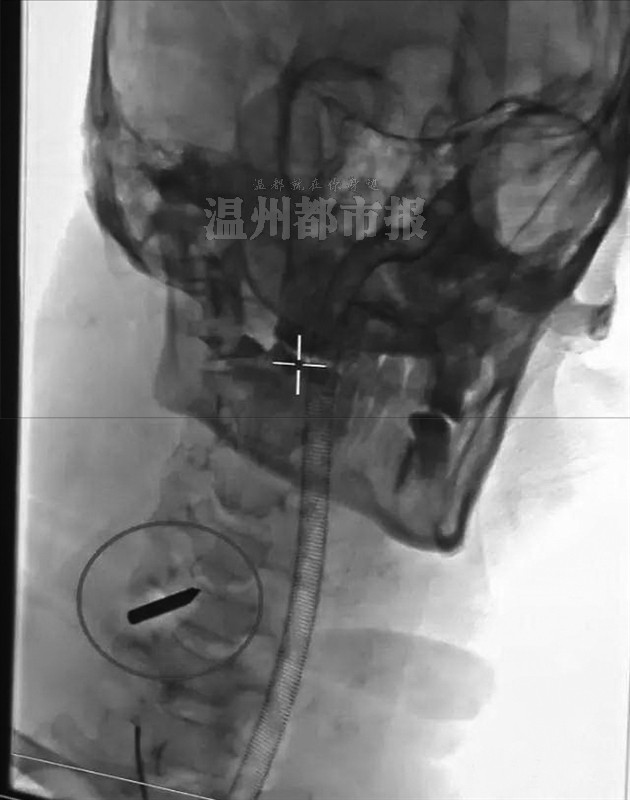

▲患者所拍的片子。下图与“铁钉”交叉物体为医生植入的栓塞。

晚上8时30分,医生全部到位。颈部平片和CT显示,“铁钉”在第五节颈椎椎管内,紧贴着硬脊膜,那里是大脑与躯干联系的重要神经所在。但让医生头痛的是,因为浓浊的淤血,他们看不见颈部动脉的损伤情况。

神经外科的尹波医师第一个登台,在介入手术室内为患者施行“右椎动脉远近端栓塞术”。医生先是在郑其仁的右侧股动脉打个小洞,然后将一根带有球囊的细丝从股动脉伸入,慢慢地往出血位置推进,在X光线下寻找出血点。找到后,医生就会释放细丝中的球囊,将出血点堵住,以求止血。